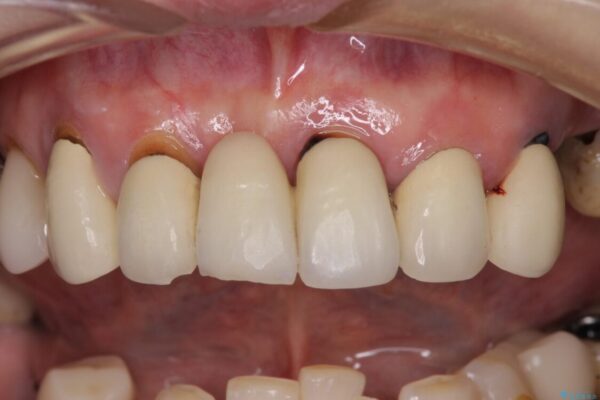

インプラント上の仮歯がボロボロになり、前歯に非常に負担のかかる状態であったため、早急に奥歯の仮歯を修復し、矯正治療、奥歯の補綴治療、前歯の補綴治療と順々に進めて行きました。

治療後

• 放置したインプラントとインビザライン 全顎リカバリー治療 治療後画像